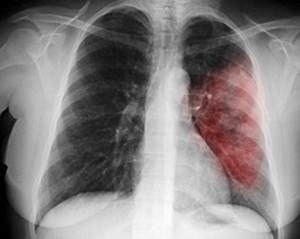

- Мальчик умер от вирусной геморрагической пневмонии, которая передается воздушно-капельным путем, - говорит педиатр Корюковской центральной районной больницы Любовь Товстоног.

- Однако говорить о вспышке или эпидемии в селе нельзя - это сезонный подъем заболеваемости. Если пневмонию своевременно диагностировать, то она успешно лечится. До случая с Денисом в Корюков-ском районе за последние 10 лет не было зафиксировано ни одной детской смерти от пневмонии.